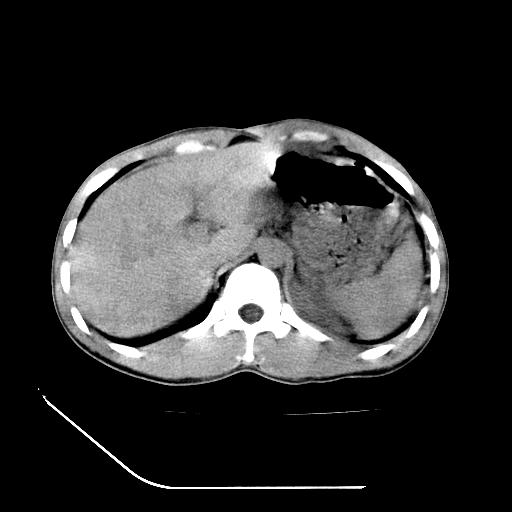

m-25y 高空堕落 12 月5号

12月7号病人尿量200ml/24h 急查双肾ct

左肾挫裂伤并肾周血肿;

肝肾间隙可见液区,建议手术探查;

左肾挫裂伤并肾周血肿

支持 : 左肾挫裂伤并肾周血肿

支持:1、左肾挫裂伤并肾周血肿;

2、少量腹水;

3、左肾旋转不良;

4、反射性肠淤张。

除了1:左肾挫裂伤并肾周血肿;

2:少量腹水

第二次ct检查后:临床医生腹水穿刺后考虑肠系膜动脉破裂,后实行剖腹探查:于空肠距离十二指肠90cm处发现肠管破裂,破裂口较小;修补后关腹。